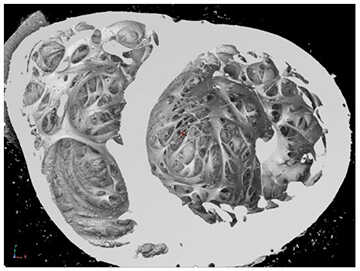

A technique for preparing the explanted hearts for CT scanning was developed. The technique included filling the heart with expandable low-density foam that supported the interior of the heart and was invisible to X-ray energies used on this program. Explanted human hearts were scanned with an X-ray tube voltage of 120 kV resulting in images with 87-micron resolution. (Figures 1 and 2) Three-dimensional morphological image processing techniques were used to isolate the heart tissue within the image and to further isolate the internal trabecular network of the left ventricle from the surrounding heart tissue. A skeletonization algorithm was developed that simplified the trabecular structure into a series of single-voxel paths with identified branch points. (Figure 3) The skeletonization allowed for measurements of properties such as number of trabeculae, and the length and central cross-sectional area of each trabecula.

Figure 1: Surface rendering of the inside of the heart. This is a view looking toward the apex of the heart with the left ventricle on the right side of the image.

Figure 2: Visualization of inside the left ventricle near the apex.